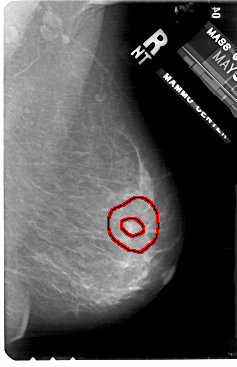

A_1906_1.LEFT_MLO

LEFT_MLO LINES 5491 PIXELS_PER_LINE 3421 BITS_PER_PIXEL 12 RESOLUTION 43.5 OVERLAY

FILE: A_1906_1.LEFT_MLO.OVERLAY

TOTAL_ABNORMALITIES 1

ABNORMALITY 1

LESION_TYPE CALCIFICATION TYPE PLEOMORPHIC DISTRIBUTION SEGMENTAL

ASSESSMENT 4

SUBTLETY 3

PATHOLOGY MALIGNANT

TOTAL_OUTLINES 1

BOUNDARY